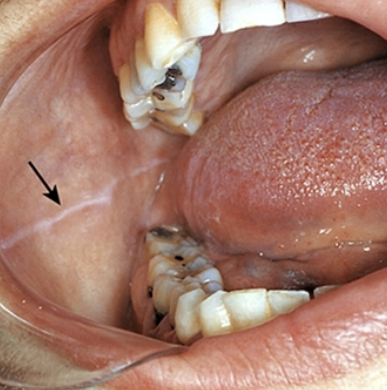

may be bilateral, can be more prominent in patients who have a clenching/ bruxing habit

linea alba

Linea Alba most common locations

anteroposterior on the buccal mucosa along the occlusal plane